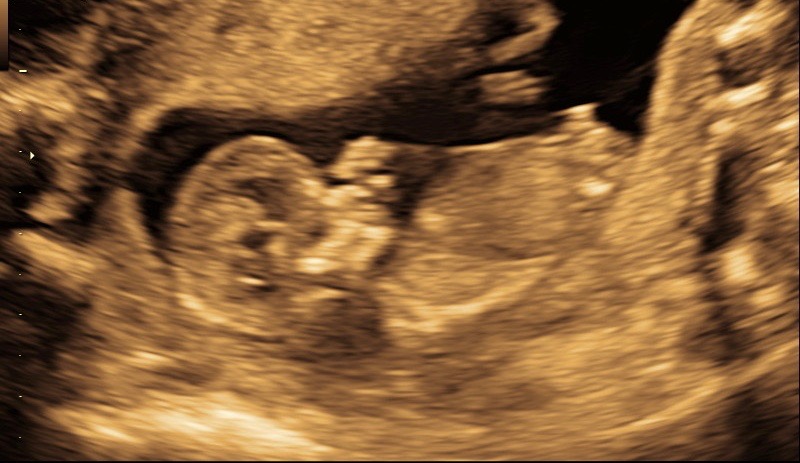

I'm a long-time lurker, first-time poster. What do you ladies think, blue or pink? Or is it too early? Thanks for any guesses!

Attachment 37750

*****EDITED TO ADD SECOND PIC, as bigpinkwish kindly pointed out first MIGHT be UC:)***

Looks boyish

Boy :)

If that's the nub I would say boy, but actually I think that's the UC...

All boy!! Congrats :happy: